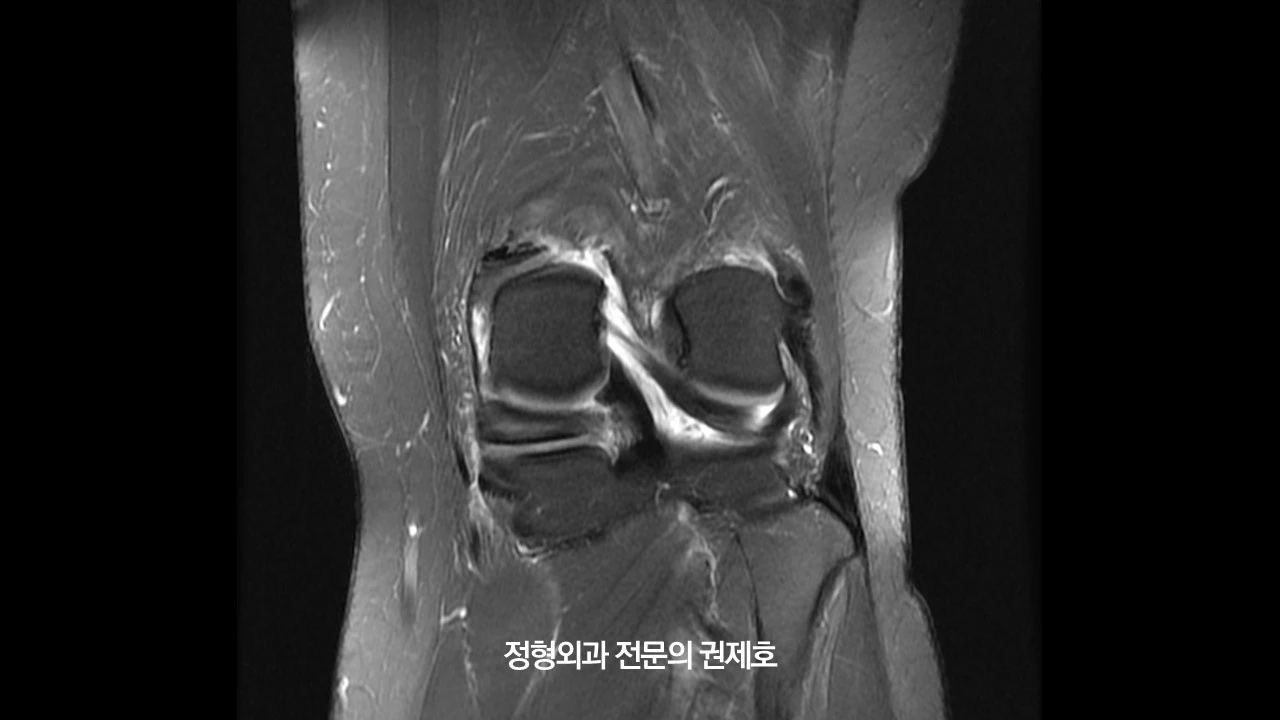

오른쪽 무릎 MRI입니다. 보시면 바깥쪽에 선천성 원판형 연골판이 존재하면서 안쪽에는 연골 손상과 함께 반월상 연골판 파열도 관찰되었습니다.